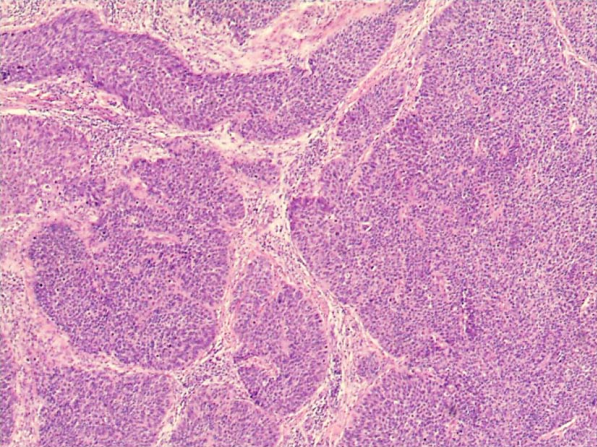

(1)显微镜检

1)微小浸润性鱗状细胞癌:指在HSIL(CIN3)基础上镜检发现小滴状、锯齿状癌细胞团突破基底膜,浸润间质。诊断标准见临床分期。

2)浸润性鳞状细胞癌:指癌灶浸润间质范围超出微小浸润癌,多呈网状或团块状浸润间质。根据癌细胞核的多形性与大小及核分裂程度等可将状细胞癌分为高(Ⅰ级)、中(Ⅱ级)、低分化(Ⅲ级)3种,这种分级法可能提供了肿瘤对化疗和放疗相关的预后信息,但目前更倾向于分为角化型和非角化型。角化型:大致相当于高分化鳞癌,细胞体积大,有明显角化珠形成,可见细胞间桥,细胞异型性较轻,无核分裂或核分裂军见。非角化型:大致相当于中分化和低分化鳞癌。细胞体积大或较小,可有单细胞角化但无角化珠,细胞间桥不明显,细胞异型性常明显,核分裂象多见。除上述最常见的两种亚型外还有以下多种亚型:乳头状鳞状细胞癌、基底细胞样状细胞癌、湿疣样癌、疣状癌、鳞状移形细胞癌和淋巴上皮样瘤样癌。

高分化鳞癌镜下观(40×) 中分化鳞癌镜下观(40×) 低分化鳞癌镜下观(40×)